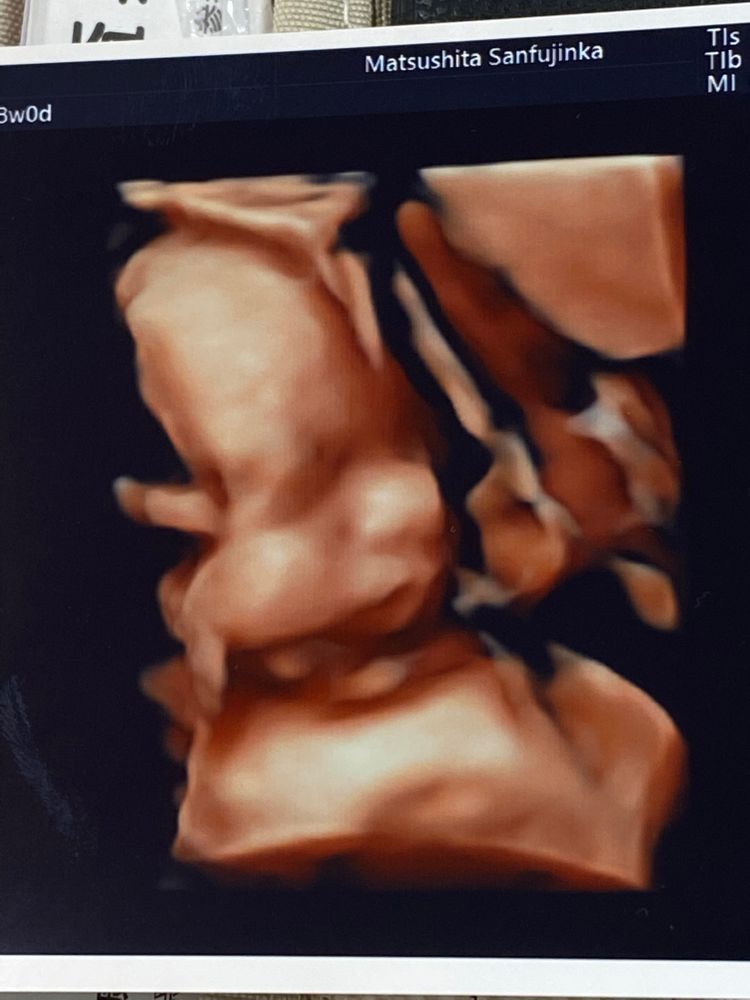

Viktoria 3 года «До чего техника дошла» 🥰😁 Копия мужа 😍 Посмотрите еще 20 записей на эту тему Лучший ответ ИЛИОНА Диагностик Экстрасенс Господи какая прелесть! Растите здоровенькими!🤗🧸🌸🎈 03.07.2022 Ответить Viktoria ИЛИОНА (Диагностик,Экстрасенс ), Спасибо ☺️ 07.07.2022 Ответить Отменить Ответить Эволюция 😁 Матрасик топпончино своими руками. Чаты Беременных Выберите чат: Январята-2026 Февралята-2026 Мартята-2026 Апрелята-2026 Майчата-2026 Июнята-2026 Июлята-2026 Августята-2026